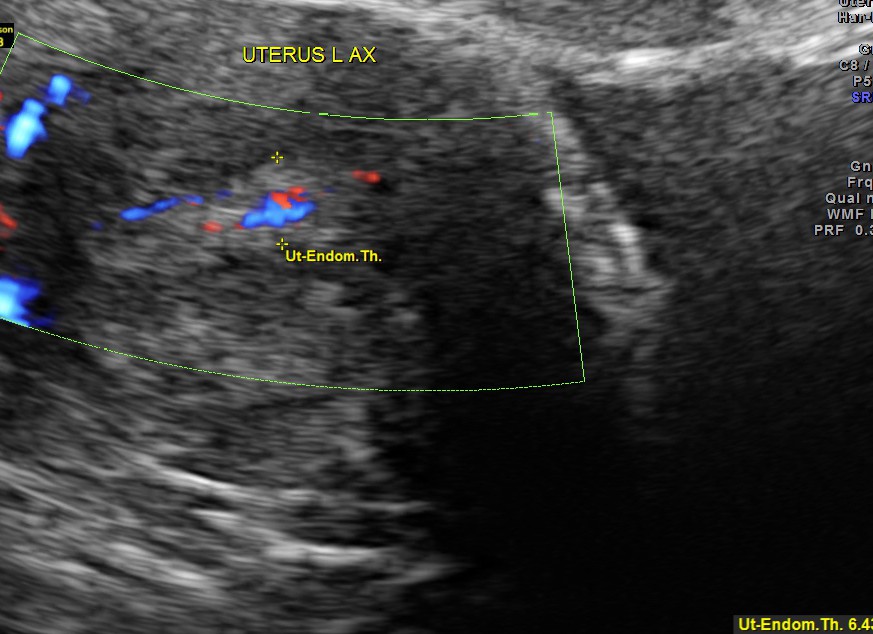

This was a 53 year old post menopausal lady who was evaluated for intermittent leucorrhoea. She had a carcinoma of breast and was operated earlier. She was on T.Tamoxifen for the past 3 years.The endometrial thickness was between 5.75 to 6.43 mms .Colour doppler showed increased vascularity.

Tamoxifen may cause the endometrium to appear thickened, irregular, and cystic. They tend to be subendometrial in location and cause subendometrial cysts that can be demonstrated at ultrasound.

Most patients tend to have a multiplicity of findings being difficult to assign a single sonographic feature to a single pathologic entity. According to one study ~50% of sonograms in those on Tamoxifen revealed an endometrial thickness of 8 mm or more.